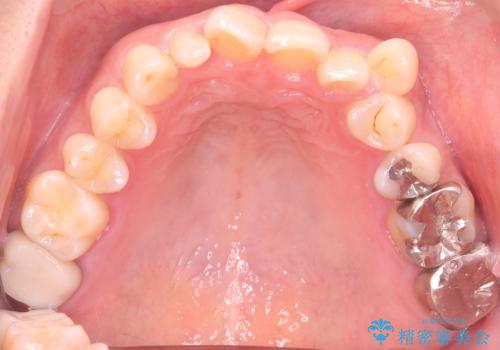

- 40代の患者様で、左上の**八重歯(犬歯の突出)**をずっと気にされていたものの、年齢的な不安から治療を迷われていたとのことでした。精密な検査の結果、左上の歯列に八重歯を収めるための十分なスペースがないことが判明。

40代は歯周組織の健康維持も重要なため、無理な拡大を避け、左上4番(第一小臼歯)を抜歯して確実にスペースを確保する計画を立てました。装置には、歯を三次元的にしっかりとコントロールでき、確実な移動が見込めるワイヤー矯正を選択。八重歯を正しい位置へ誘導し、健康的で美しい口元を目指しました。